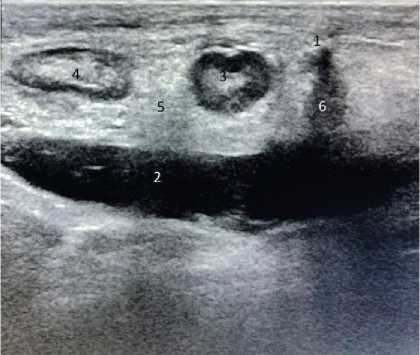

Обследование 242 пациентов показало, что диагностика паховой грыжи у мужчин не сложна. Клинические проявления заболевания позволяли во время осмотра установить диагноз, а при УЗИ оценить состояние тканей в паховых областях, локализацию грыжи (прямая или косая) и определить содержимое грыжевого мешка, что имело значение для установления сроков выполнения операции. У женщин были проблемы ранней диагностики неосложнённой грыжи при астеническом телосложении и у гиперстеников, страдающих ожирением. На ранних сроках развития грыжи женщины предъявляли жалобы на боли в паху при отсутствии над ним опухолевидного образования. При этом из-за особенностей расположения наружного отверстия пахового канала в проекции половых губ определить грыжу при пальцевом исследовании было не всегда возможно. Объяснить эту особенность можно тем, что при косой паховой грыже, спускающейся через глубокое паховое кольцо, грыжевой мешок расслаивает круглую связку матки, имеющей малый диаметр, не выходит за её размеры. При прямой паховой грыже грыжевой мешок смещается параллельно круглой связке матки, подходит к наружному паховому кольцу и располагается под ним в виде опухолевидного образования, что позволяет клинически поставить диагноз. У пациенток с ожирением из-за избытка жировой ткани в надлобковой области определить грыжевой мешок при отсутствии клиники ущемления, выходящий из наружного отверстия пахового канала, практически очень сложно, что для установления диагноза требует применения инструментальных методов исследования. Применение УЗИ позволяло установить и подтвердить диагноз у пациентов с паховой грыжей. На рисунках 1 и 2 представлены результаты УЗИ у пациента Н., 37 лет, с двухсторонней паховой грыжей, которые позволили подтвердить диагноз и выполнить операции по поводу паховых грыж открытым способом с двух сторон. На рисунке 3 представлены результаты УЗИ пациентки Н., 45 лет; диагноз – правосторонняя косая паховая грыжа: вид грыжевого мешка, расположенного в круглой связке матке.

Рисунок 3. Пациентка Н., 45 лет. Изображение правосторонней косой паховой грыжи при ультрасонографическом исследовании: 1 – грыжевой мешок, расположенный в круглой связке матки Figure 3. Patient N., 45 years old. Ultrasonographic image of a rightsided oblique inguinal hernia: 1 – hernial sac located in the round ligament of the uterus